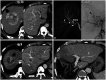

Yttrium-90 transarterial radioembolization (TARE) has emerged as a valuable treatment option for hepatocellular carcinoma (HCC) and is being increasingly incorporated into clinical guidelines. Recent advancements in dosimetry, including personalized dosimetry and multi-compartment modeling, have significantly improved tumor response and clinical outcomes. Although high tumor-absorbed doses are associated with better oncologic control, careful dose adjustment is essential for minimizing toxicity to normal liver tissue and lungs. This review explores the key aspects of TARE dosimetry, including single- and multi-compartment modeling, differences between resin and glass microspheres, dose-response relationships, and strategies to mitigate hepatotoxicity and radiation pneumonitis. Various clinical applications of TARE have been discussed, ranging from curative-intent radiation segmentectomy and lobectomy to palliative treatment of diffuse and macrovascular invasion-associated HCCs. In South Korea, where cadaveric liver transplantation is limited, a multidisciplinary approach is particularly important for optimizing treatment strategies and preserving liver function for potential future interventions. As dosimetry continues to evolve, further research is required to refine dose optimization protocols and validate their clinical impact in different patient populations, including those in South Korea.